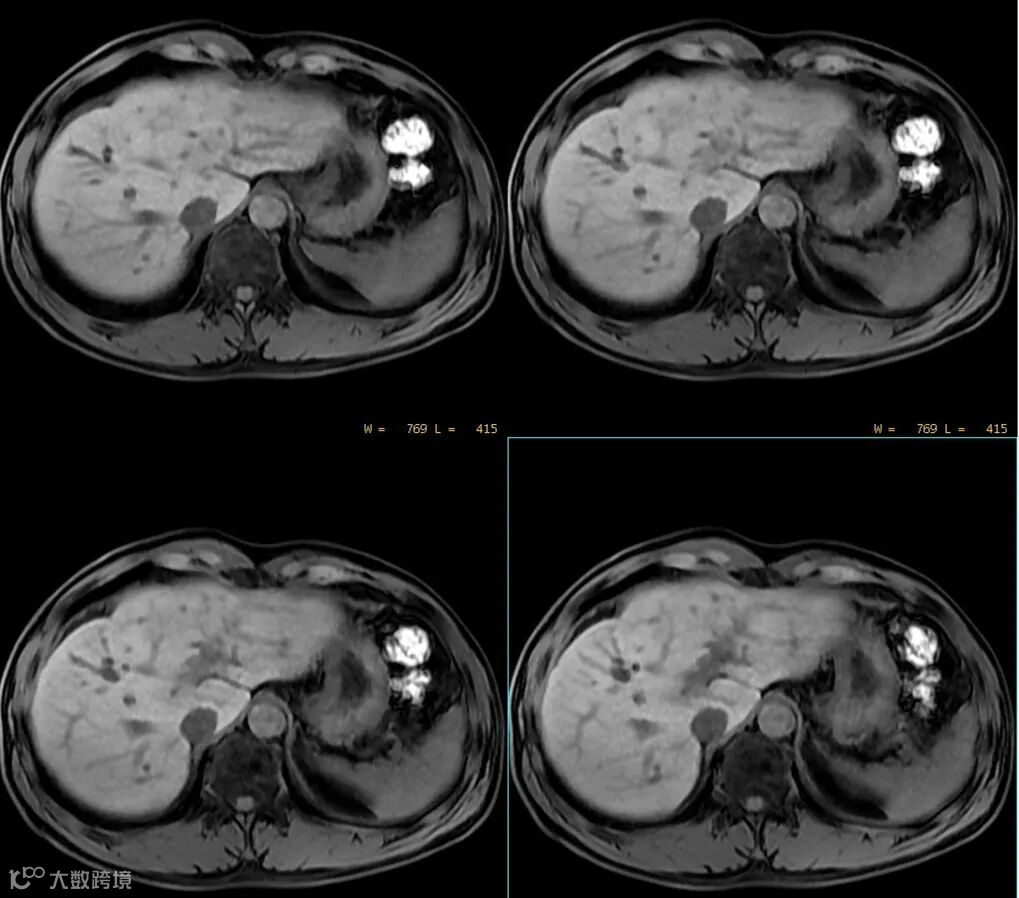

MRI图像上的组织信号与诸多因素相关,如序列、参数、组织本身的状态等。所以应首先要看是什么序列,使用的什么参数,目标组织的状态是怎样的。 -

MRI上的信号是相对的,没有绝对的高与低,而要看与谁比,在解读MRI图像信号时要选取信号相对稳定的组织作为参照对比,如肌腱,脑脊液。 -